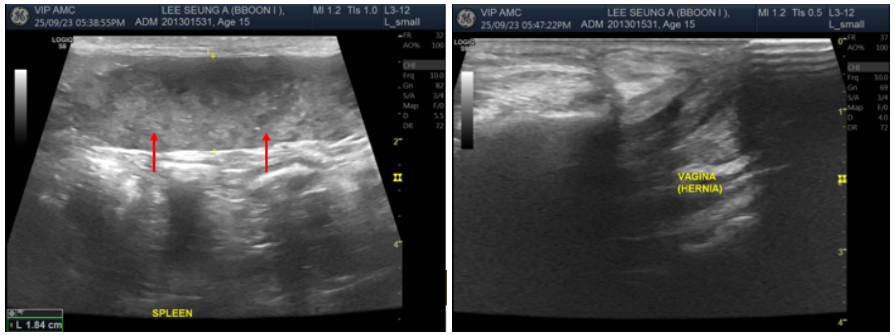

초음파 검사상 CKD, 간 결절, 담낭 슬러지 등 몇 가지 기저질환이 확인되었으며, 비장 실질의 불균질한 변화(↑)와 비장 결절도 관찰되었습니다. 악성 종양에 의한 비장 실질 변화 가능성을 고려하여, 마취 시 FNA를 함께 진행하기로 하였습니다.

수술 중 확인한 결과, 꿍이의 질탈 부위는 질 종괴의 탈장이었던 것으로 확인되었습니다.